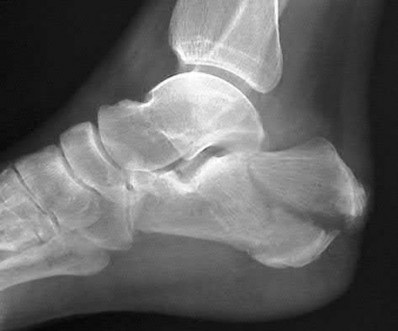

Figure A is an AP radiograph of a posterior knee dislocation. Figure B is a lateral showing the same injury.